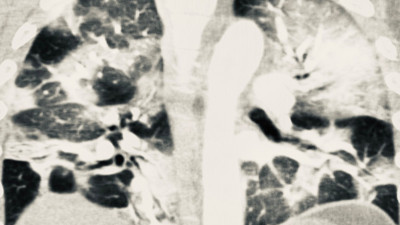

Aşı olanlarda korona virüs akciğere zarar vermiyor! İşte 2 kişiye ait tomografi sonuçları Radyoloji Uzmanı Prof. Dr. Güner Sönmez, 35 ve 42 yaşında Covid olmuş iki insanın akciğer filmleri hakkında dikkat çeken bir değerlendirmede bulundu.